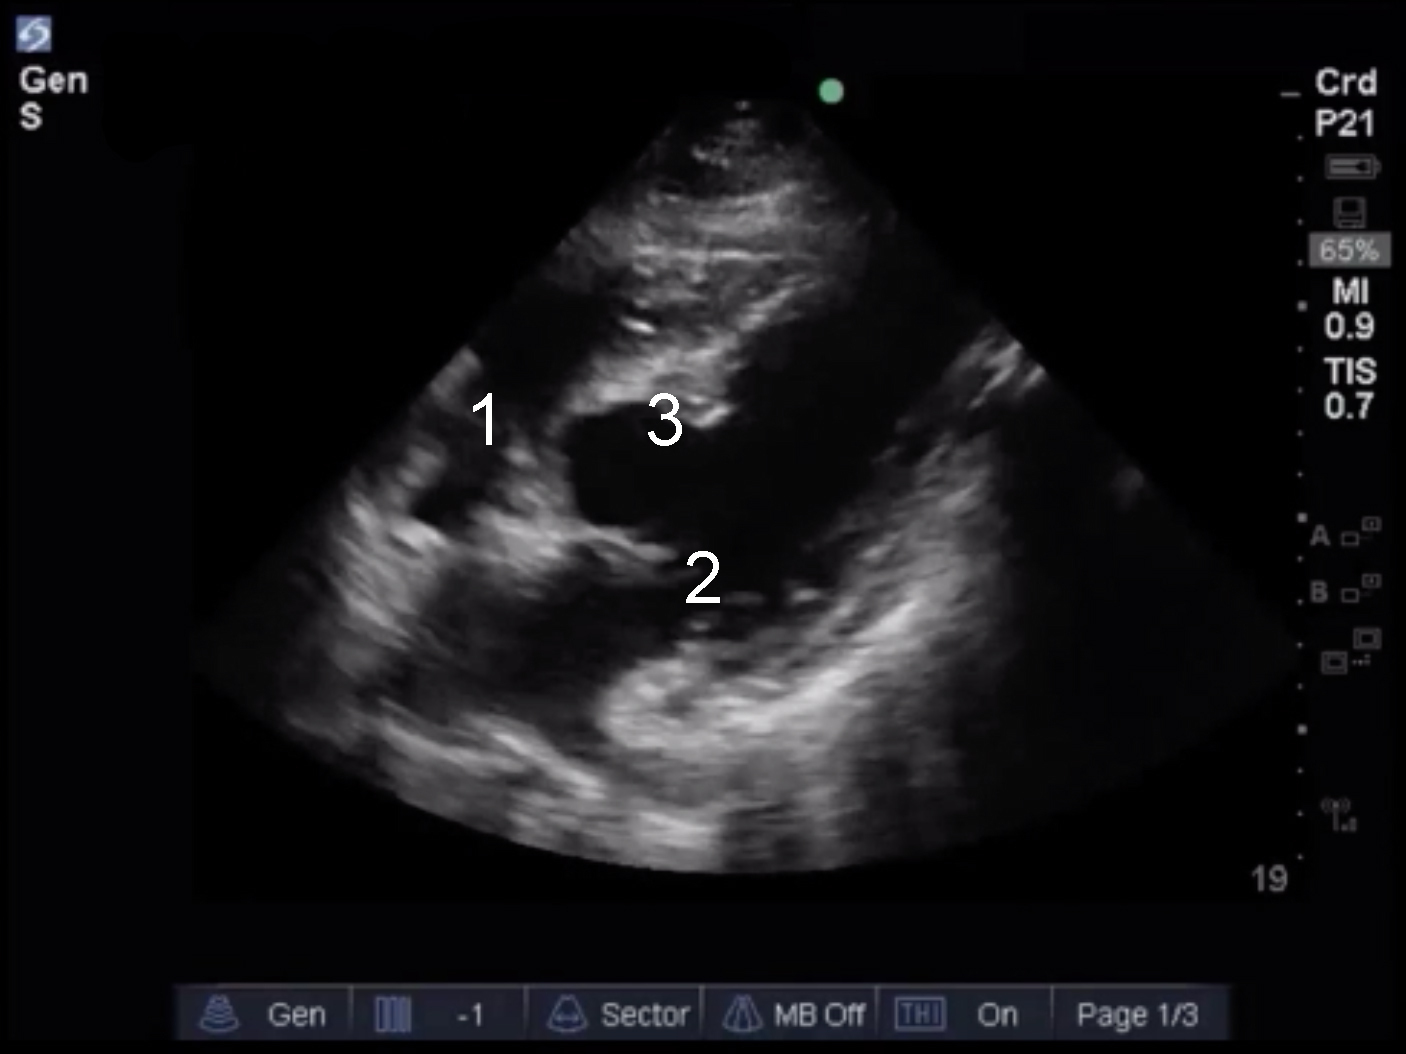

Cardiac 2 Valves Case 4 Image

Tricuspid Valve

Mitral Valve

Septum